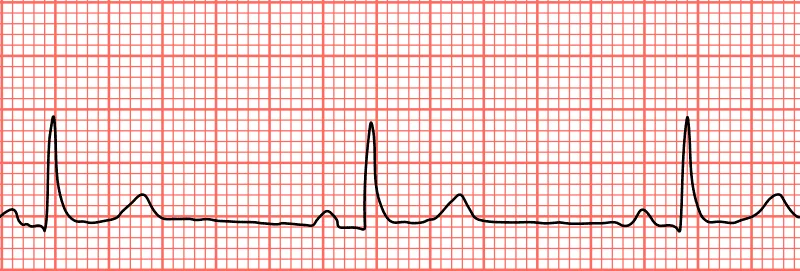

心率過低,也稱為心率過緩,是指在靜息狀態下,心跳速率低於每分鐘60次。正常心跳速率通常介於60到100次/分鐘之間。

心率過低